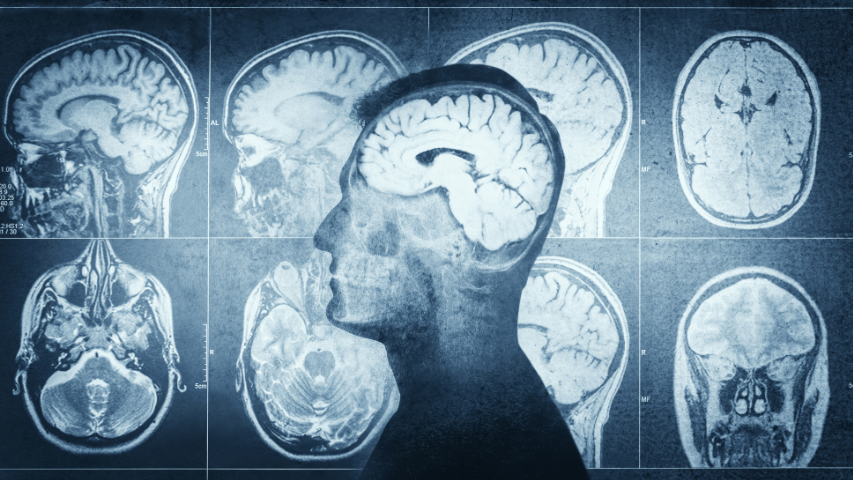

Recovery from epilepsy surgery is both physical and neurological. The brain requires time to adjust to changes caused by the removal or disconnection of seizure-producing tissue. It’s normal to experience temporary fatigue, mild confusion, or difficulty concentrating in the first few weeks.

These effects usually improve as brain networks adapt. The body’s healing process also varies depending on the type of surgery. Open resections involve a larger incision, which may take several weeks to heal, while minimally invasive procedures like laser ablation leave only a small scar.